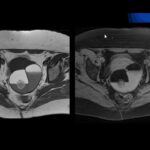

O cisto mamário é um problema que aterroriza muitas mulheres na faixa entre 35 e 40 anos. Não há motivos para pânico, pois é uma alteração benigna da estrutura da mama. O cisto é uma alteração que acontece, com pequenas bolinhas de líquido dentro da mama. Obviamente, essas bolinhas podem ficar todo o tempo pequenas ou podem crescer, mas na verdade é uma bolinha de líquido. Em muitas vezes, não sofre transformação para câncer, não tem nada absolutamente a ver com o câncer de mama.

Ela tem que se cuidar sem temores, não está com estresse por isso, mas procurar fazer a rotina de avaliação médica. O período para o tratamento dos cistos existem duas possibilidades: os microcistos da manhã, como a gente chama, são todos considerados normais na terra sendo uma coisa própria da mama. Se eles crescem 2 centímetros e dependendo do conteúdo, desse jeito, agente pode precisar fazer uma função que é o que coloca uma das teses na pele do consultório médico. Não precisa internamento internação, danese na pele introduz agulhinha esse livro Israel tratamento também javalis. Isto é o livro se precisa de alguma coisa, mas quando ele é grande, isso é grande e contém sangue no seu interior é um indicativo de que se precisa ser retirado um cisto grande entendem-se 1 63 cêntimos ou mais quem sabe indicativos em breve cooperar.